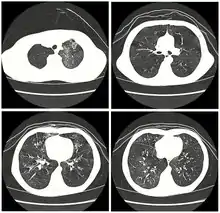

High-resolution CT scan of a child with post-infectious bronchiolitis obliterans showing glass pattern with air trapping and bronchial thickening

Typically found in young children and is the most common cause at this age.[31] Generally occurs after a viral infection of adenovirus (types 3, 7, and 21), measles (rubeola), mycoplasma, CMV, influenza, and parainfluenza.[4][6] Swyer-James syndrome is a rare complication of bronchiolitis obliterans caused by measles or adenovirus.[32] Post-infectious bronchiolitis obliterans is most common in the southern hemisphere particularly in countries such as Brazil, Argentina, Australia, Chile and New Zealand.[33] There was a large prevalence of the disease in these areas during the 1990s and early 2000s. In one hospital in Buenos Aires, the Ricardo Gutiérrez Children's hospital, the disease accounted for 14% of their inpatient respiratory population from 1993 to 2002.[33] As such, much of the information about post-infectious bronchiolitis obliterans has come from research out of South America. The most significant risk factors for the disease are infection with adenovirus and the need for ventilator support.[33] In contrast with another cause of bronchiolitis obliterans in children, Steven's Johnson's syndrome, post-infectious bronchiolitis obliterans tends to be a chronic but non-progressive disease.[31] The disease can have varying impact on children and their quality of life, which has been studied by lung function tests, as well as their exercise tolerance.[34] Children with lower lung function based on their pulmonary function testing, have lower exercise tolerance, which compounds the impact of the disease on cardiovascular function as they are not able to maintain age appropriate aerobic fitness.[34] This ultimately affects their activities of daily living (ADLs) and their quality of life going forward.[34]